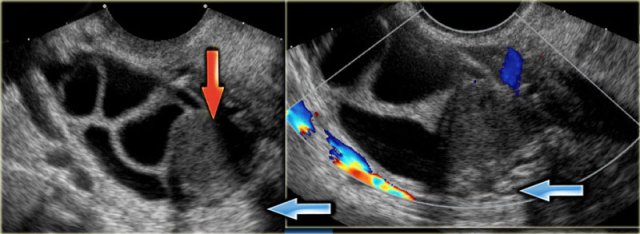

The ultrasound images show multiple simple and one complex right ovarian lesion (red arrow).

The latter demonstrates diffuse low-level echos and no flow on Doppler.

Note that there is a good through transmission (blue arrow).

These findings indicate the presence of a hemorrhagic cyst.